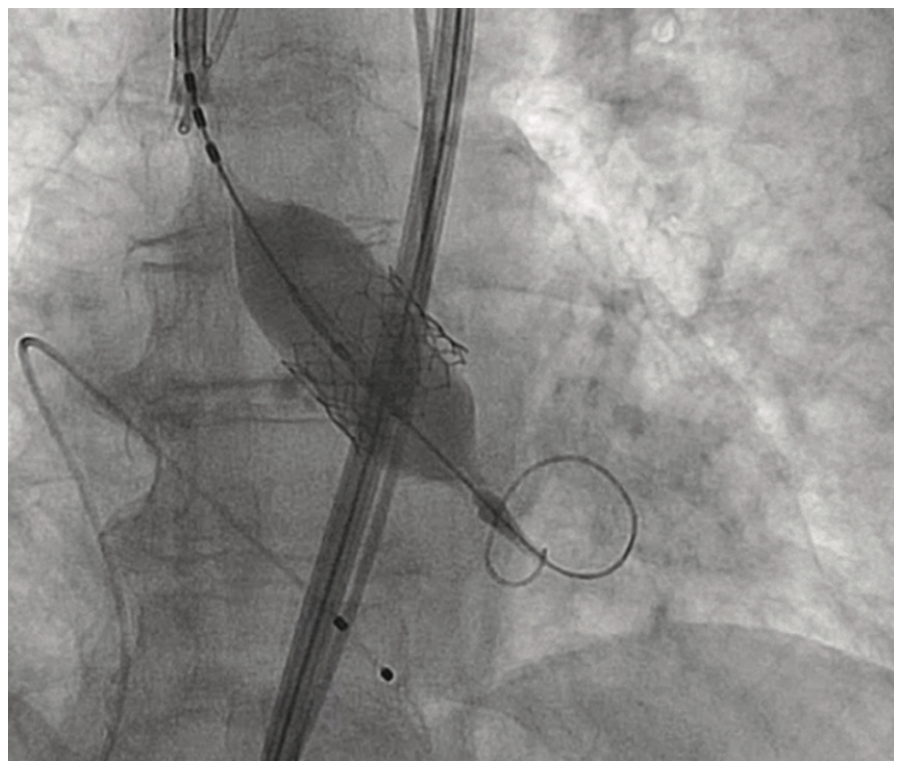

An 81-year-old female with symptomatic severe aortic stenosis, logistic EuroSCORE I (European System for Cardiac Operative Risk Evaluation) of 14.46%, EuroSCORE II of 3.44%, and Society of Thoracic Surgeons (STS) estimated surgical mortality of 3.371%, underwent TAVR. Transthoracic echocardiogram (TTE) showed a heavily calcified aortic valve with a mean gradient of 68 mmHg, aortic valve maximum velocity (Vmax) of 4.2 m/sec, calculated aortic valve area of 0.8 cm2, and normal left ventricular systolic function. Computed tomography angiography (CTA) demonstrated heavily calcified aortic root, leaflets, and annulus. Transfemoral implantation of a 23 mm Sapien 3 (Edwards Lifesciences) valve was performed (Figures 1-2). Using a 20 mm balloon for pre-dilation, the valve was implanted successfully in a 50-50 position (Figure 3). The immediate post-deployment aortogram showed leakage of dye outside the left sinus with no evidence of cardiac tamponade. Despite that fact, the patient developed immediate hemodynamic collapse. QRS widening and ST-elevation were visible on the monitor. Narrowing of the left main coronary artery (LMCA) with reduced TIMI flow (0-1) was evident in angiographic images (Figures 4-5). The patient had a cardiac arrest, cardiopulmonary resuscitation was initiated, and she went into cardiogenic shock. The patient stabilized with the placement of venoarterial extracorporeal membrane oxygenation (VA-ECMO) and the insertion of the Impella device (Abiomed) (Figure 6). An emergent percutaneous intervention was performed within minutes from collapse by the deployment of two drug-eluting stents from the LMCA into the left anterior descending (LAD) coronary artery (Figure 7) using the Culotte technique with final kissing-balloon dilatation. After the restoration of coronary flow, the patient was admitted to the cardiothoracic intensive care unit. She remained stable. The ECMO and Impella implant was removed after 7 days. Postprocedure on day 14, the patient was discharged to a rehabilitation facility. Echocardiography showed a well-functioning valve with acceptable residual gradient and mild to moderate paravalvular leak.